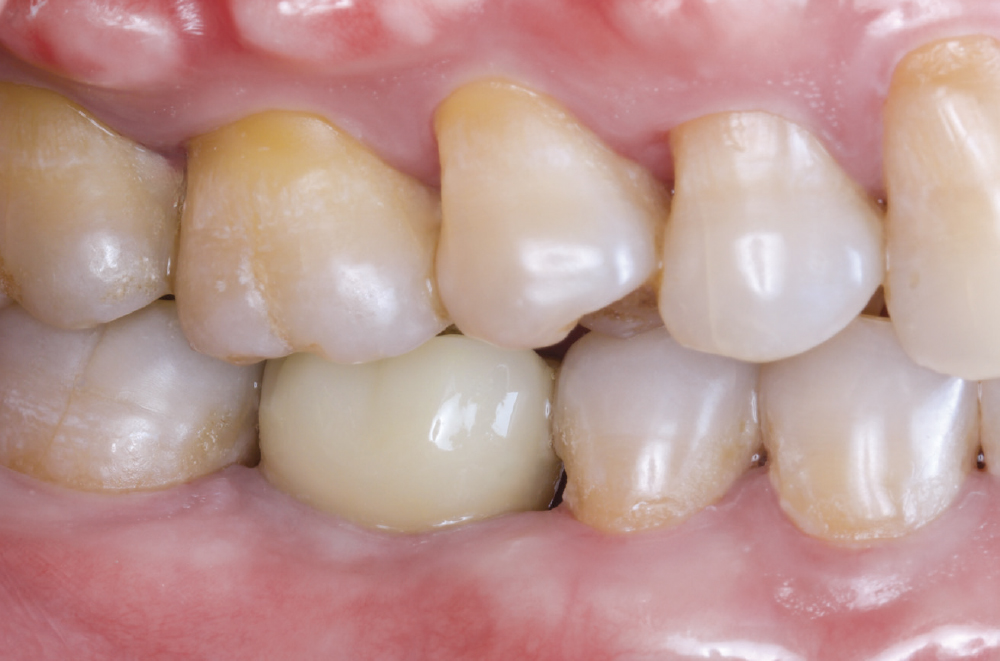

Implant post in socket

Finished Implant Restoration

Practice and Ask Questions. Excellence in digital scanning is not achieved through technology alone — it requires good training, clear communication and deliberate practice. While there will always be some learning curves and occasional challenges, having a strong working rapport with your laboratory team and establishing clear protocols helps you navigate setbacks with confidence.